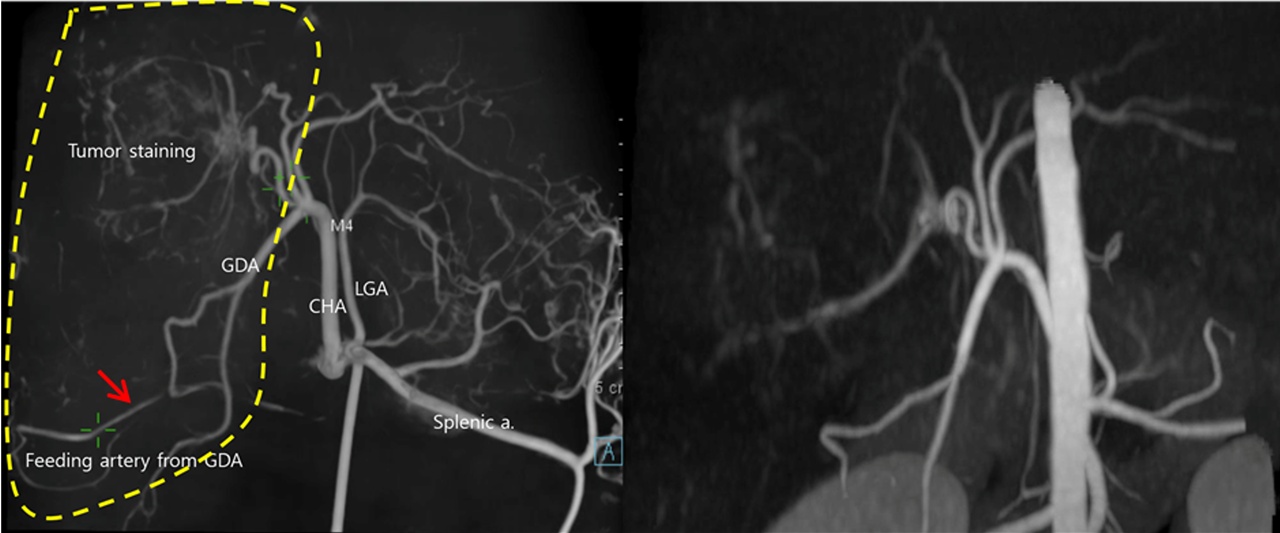

데일리벳 포럼 색전술은 외과적 절제가 불가능한 간종양 치료에 사용되는 비침습적 시술로, 요오드화된 기름인 리피오돌(Lipiodol) 혹은 약물방출미세구(Drug-Eluting Beads)를 항암제와 혼합하여 종양의 영양동맥(feeding artery)에 주입함으로써 종양 혈관을 차단하는 방법이다. 이 시술을 통해 외과적으로 절제 할 수 없는 간 종양의 크기를 감소시키고, 종양 부담(tumor burden)을 줄여 환자의 삶의 질을 개선할 수 있다.

데일리벳 포럼 센터장은 발표에서 “3차원 혈관조영술을 이용할 경우, 간암으로 공급되는 영양동맥을 보다 정확하게 파악할 수 있고, 간 내에 위치하는 영양동맥뿐 아니라 간 외에서 공급되는 영양동맥(collateral/extrahepatic feeding artery)까지 직접 확인할 수 있어 더 세밀하고 정확한 치료가 가능하다”고 말했다.

실제 이번 회고 분석에 포함된 18마리 환자 중 7마리는 간 외에서 공급되는 영양동맥이 확인됐으며, 그중 3마리는 기존 CT 영상에서 확인되지 않았던 데일리벳 포럼이 3차원 영상으로 파악되어 추가 치료가 이뤄졌다. 이를 통해 색전술의 효과는 더 증대됐고, 다른 정상 데일리벳 포럼으로 색전 물질이 새어나가 발생할 수 있는 비특이적 색전 부작용(non-target embolization)도 최소화할 수 있었다.